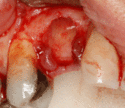

An incision is made across the area and the flap of gingiva is opened to show the bone of the jaw.

An incision is made across the gingiva, and the flap of tissue is reflected to show the bone of the jaw.